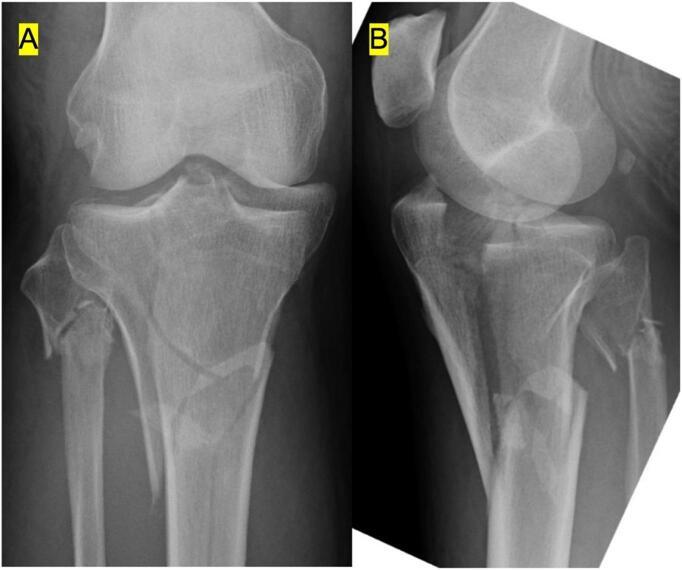

Anterior cruciate ligament reconstruction with retained internal fixation hardware for treating Schatzker type V tibial plateau fracture: Two case reports.

Despite the high incidence of anterior cruciate ligament injury in patients with tibial plateau fractures, we found no reports about anterior cruciate ligament reconstruction with retained internal fixation hardware for these fractures. Herein, we report 2 male patients with Schatzker type V tibial plateau fractures and describe the use of retained hardware for internal fixation in tibia. The patients underwent anterior cruciate ligament reconstruction using outside-in technique for the femoral tunnel. Throughout the follow-up, no radiological symptoms of suspected knee osteoarthritis were observed. Accordingly, surgical intervention can be reduced by creating an independent femoral tunnel.

尽管胫骨平台骨折患者前交叉韧带损伤的发生率很高,但我们未发现有关这些骨折保留内固定硬件进行前交叉韧带重建的报道。在此,我们报告2例Schatzker V型胫骨平台骨折男性患者,并描述在胫骨内固定中使用保留硬件的情况。患者采用经外向内技术建立股骨隧道进行前交叉韧带重建。在整个随访过程中,未观察到疑似膝关节骨关节炎的放射学症状。因此,通过创建独立的股骨隧道可减少手术干预。